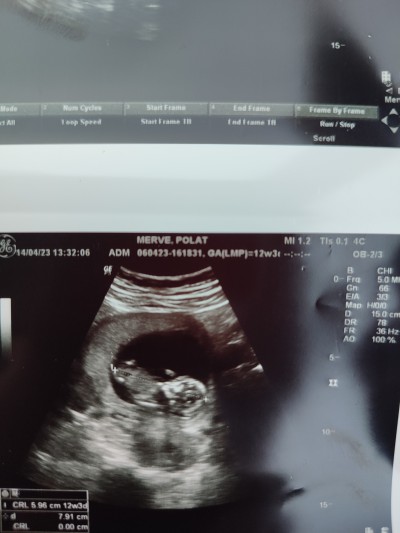

12+3 günlük doktorumuz baktı uyuyordu birşey gormedi sizce cinsiyeti nedir

Gebelik haftası 12+3 günlük doktorumuz baktı uyuyordu birşey gormedi sizce cinsiyeti nedir

Benim de 12 +3 te bugün bugün gittim doktora bacak arasından baktı %90 erkek dedi doktor görünüyor aslında yani benim bebeğimde çok hareketli değil di kontrol de ama doktor bacak arasına görebildii

Hiç yorum yapmadı uyuyordu uyandiramadik  Kız veya erkek demedi yorum yapmadı